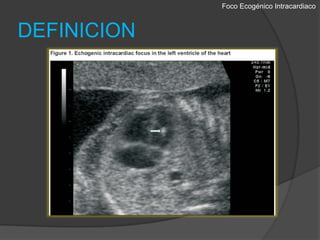

Foco EcogénicoIntracardiacoDEFINICIONEl foco ecogenicointracardicos se describe como áreas de  ecogenicidadcomparable a la del hueso, en la región de los músculos papilares en cualquiera de los ventrículos. 1-288% en el ventrículo izquierdo, el 5% en el derecho, y el 7% biventricular. 3Se encuentran del 1,5 al 4% de los embarazos normales.Obstetricia Integral Siglo XXI. Universidad Nacional, Facultad de Medicina, Departamento de Obstetricia y GinecologiaDiagnostico Prenatal con Ultrasonido. Jaime Arenas Gamboa, Javier Andrés Ramírez Martínez.

Foco EcogénicoIntracardiacoDEFINICIONUtilizando un transductor de frecuencia apropiada (5 MHz) y ajustando la ganancia, el foco ecogénico debe visualizarse en la vista estandar de cuatro camaras en un estudio ecográfico habitual.El foco debe ser visto desde varios angulos para asegurarse de que no corresponde con reflexiones especulares de los musculos papilares.Obstetricia Integral Siglo XXI. Universidad Nacional, Facultad de Medicina, Departamento de Obstetricia y GinecologiaDiagnostico Prenatal con Ultrasonido. Jaime Arenas Gamboa, Javier Andrés Ramírez Martínez.

Foco EcogénicoIntracardiacoDEFINICIONUn sistema de graduación se ha propuesto comparando la ecogenicidaddel foco intracardíacocon la del hueso circundante 4 :Grado 1 con ecogenicidad aumentada ligeramente menor al huesoGrado 2 con ecogenicidad igual a la del hueso Grado 3 con ecogenicidad mayor a la del huesoObstetricia Integral Siglo XXI. Universidad Nacional, Facultad de Medicina, Departamento de Obstetricia y GinecologiaDiagnostico Prenatal con Ultrasonido. Jaime Arenas Gamboa, Javier Andrés Ramírez Martínez.

Foco EcogénicoIntracardiacoDEFINICIONEl focoecogenicointracardicos se describe como áreas de ecogenicidadcomparable a la del hueso, en la región de los músculos papilares en cualquiera de los ventrículos. 1-288% en el ventrículo izquierdo, el 5% en el derecho, y el 7% biventricular. 3Se encuentran del 1,5 al 4% de los embarazos normales.Obstetricia Integral Siglo XXI. Universidad Nacional, Facultad de Medicina, Departamento de Obstetricia y GinecologiaDiagnostico Prenatal con Ultrasonido. Jaime Arenas Gamboa, Javier Andrés Ramírez Martínez.

Foco EcogénicoIntracardiacoDEFINICIONUtilizando un transductorde frecuencia apropiada (5 MHz) y ajustando la ganancia, el foco ecogénico debe visualizarse en la vista estandar de cuatro camaras en un estudio ecográfico habitual.El foco debe ser visto desde varios angulos para asegurarse de que no corresponde con reflexiones especulares de los musculos papilares.Obstetricia Integral Siglo XXI. Universidad Nacional, Facultad de Medicina, Departamento de Obstetricia y GinecologiaDiagnostico Prenatal con Ultrasonido. Jaime Arenas Gamboa, Javier Andrés Ramírez Martínez.

Foco EcogénicoIntracardiacoDEFINICIONUn sistema degraduación se ha propuesto comparando la ecogenicidaddel foco intracardíacocon la del hueso circundante 4 :Grado 1 con ecogenicidad aumentada ligeramente menor al huesoGrado 2 con ecogenicidad igual a la del hueso Grado 3 con ecogenicidad mayor a la del huesoObstetricia Integral Siglo XXI. Universidad Nacional, Facultad de Medicina, Departamento de Obstetricia y GinecologiaDiagnostico Prenatal con Ultrasonido. Jaime Arenas Gamboa, Javier Andrés Ramírez Martínez.